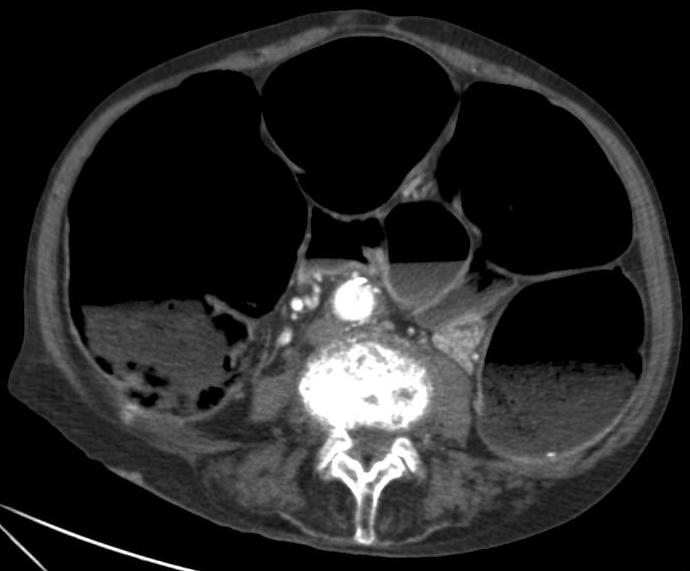

가성 장폐색 증후군은 임상적 양상에 따라 급성 또는 만성으로 분류된다. 급성 대장 가성 장폐색(ACPO; Acute Colonic Pseudo-Obstruction)은 때때로 오길비 증후군이라고도 불리며, 대장이 심하게 확장되는 특징을 보인다. 적절한 감압 조치가 이루어지지 않으면 장 천공, 복막염 및 사망에 이를 수 있는 위험이 있다. 만성 장 가성 폐쇄(Chronic Intestinal Pseudo-Obstruction)는 이름 그대로 만성적인 경과를 보이는 질환이다.[24]